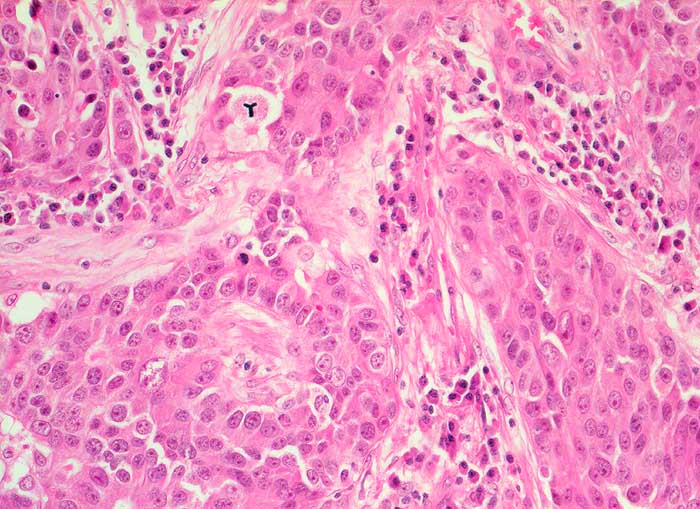

PathoPic ID 5729 - Seminommetastase

Seminommetastase

maligner Tumor

Lunge

Lunge, Mediastinum mit Thymus

Solide Tumorzellstränge umgeben von plasmozellulär infiltriertem Stroma. Grosse Tumorzellen mit reichlich eosinophilem Zytoplasma und vesikulären Kernen mit prominenten Nukleoli. Atypische Mitose (Mercedesstern).

Lungenrundherd. Status nach Semikastration wegen Seminom.

Histologie

200